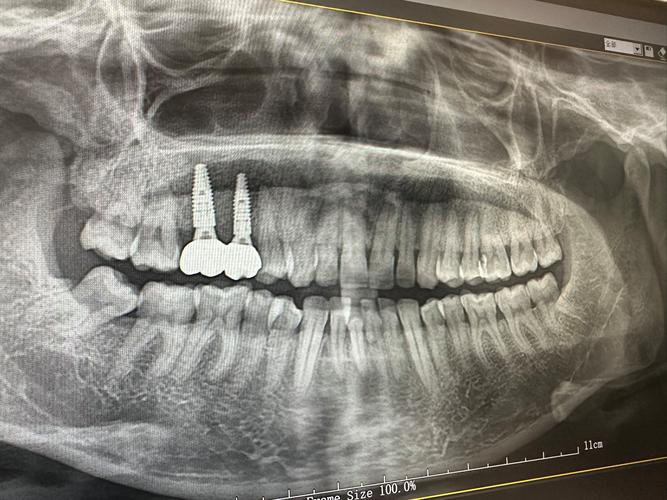

种植牙的流程通常分为术前检查、种植手术、牙冠修复及术后维护四个阶段,术前检查是关键,需通过口腔CT、全景片等评估牙槽骨的密度、高度及宽度,若骨量不足,可能需进行骨粉骨膜移植,这一阶段约需1-2周,种植手术一般在局部麻醉下进行,医生在牙槽骨制备窝洞后植入种植体,手术时间约30分钟至1小时,术后无需住院,恢复期约1周,随后进入骨结合期,即种植体与牙槽骨融合,这一过程需3-6个月,具体时间与个人骨质状况相关,骨结合完成后,安装基台并取模制作牙冠,牙冠材料全瓷冠为主,美观耐用,约1-2周即可完成最终修复,术后维护需定期复查,保持口腔卫生,避免咬硬物,种植牙的使用寿命与日常护理密切相关。

种植牙的核心是通过外科手术将纯钛种植体植入牙槽骨内,模拟天然牙根的功能,再安装牙冠,实现咀嚼、美观的双重恢复,与活动假牙、固定桥相比,种植牙不损伤邻牙,能刺激牙槽骨避免萎缩,且使用寿命长,若维护得当,可陪伴患者数十年,南京市口腔医疗机构普遍采用国际主流的种植系统,如瑞典Nobel、瑞士Straumann、韩国Osstem等,这些系统生物相容性好,骨结合率高,成功率达95%以上。